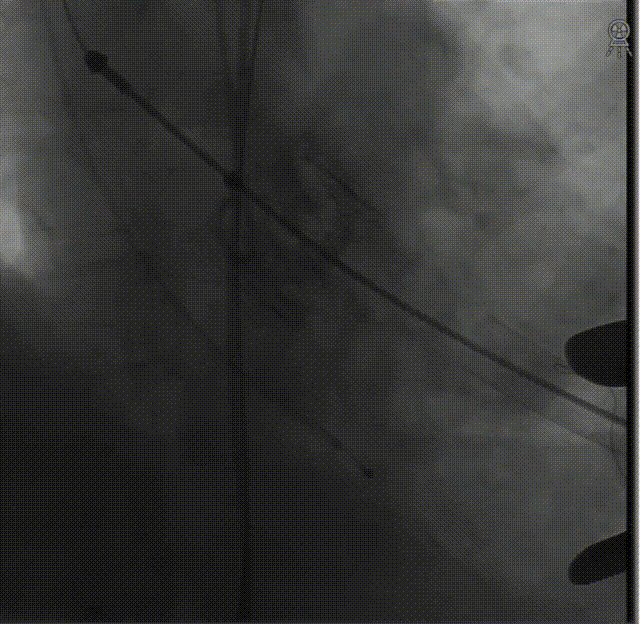

降落瓣膜件,完成释放:

复查根部造影,未见明显反流:

食道超声显示瓣架圆形展开,位置合适,未见显著反流: